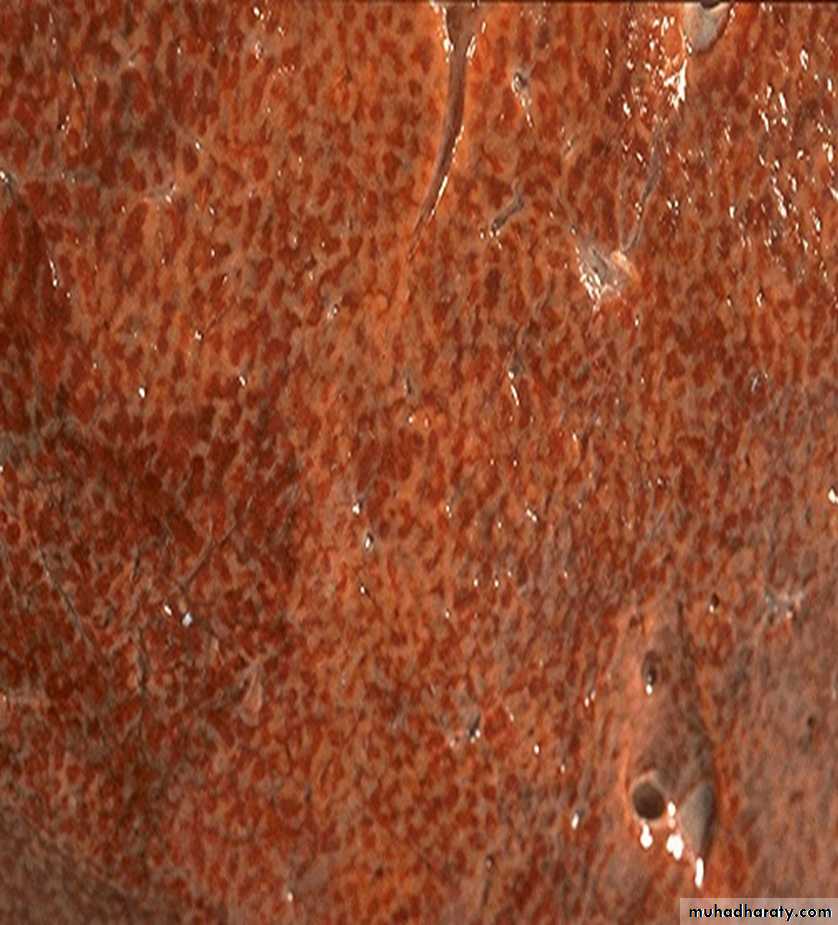

60 years male with "right sided" heart failure. (liver)

Description and diagnosischronic passive congestion of the liver. dark red congested regions that represent accumulation of RBC's in centrilobular regions.